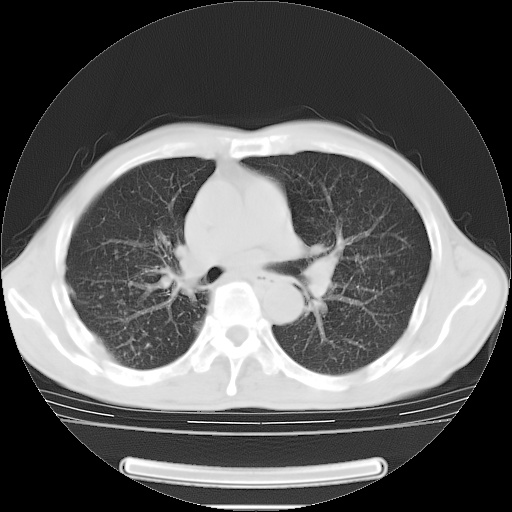

男性患者,63岁。右侧胸背部疼痛2月,加重一周。

考虑:右肺中央型肺癌并右肺下叶不张;两肺尖继发性肺结核。

还有纵隔多处肿大淋巴结及肋骨的改变、两肺多发结节灶。

考虑右中心型肺癌并右下肺不张,肺及纵隔,左肋骨转移。

右肺下叶支气管狭窄闭塞,右下肺不张,气管前间隙淋巴结肿大,两上肺散在分部粟粒灶,沿肺血管支气管束分部,血管支气管束走形较为光滑。考虑右肺中心型肺癌合并肺不张,纵隔淋巴结转移,两上肺癌性淋巴管炎

右肺下叶中心性肺癌并纵隔淋巴结转移,左侧肋骨转移。双肺上叶继发性结核表现。

1)右肺下叶中心性肺癌并纵隔淋巴结转移,两肺转移,左侧肋骨转移。2)双肺上叶继发性结核。

右肺下叶中心性肺癌并纵隔淋巴结及两肺、左侧肋骨转移。双肺上叶继发性结核表现。